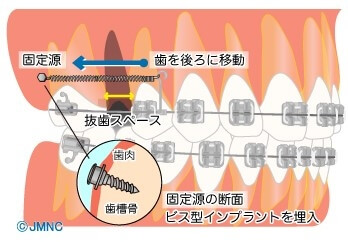

ガミースマイルの治療

ガミースマイルとは、笑ったときに上の歯ぐきが見えすぎてしまう状態のことです。外科手術で歯ぐきや歯の周りの骨を整形することで改善が期待できますが、軽度であればアンカースクリューを使った矯正治療でも改善が可能です。

ガミースマイルとは、笑ったときに上の歯ぐきが見えすぎてしまう状態のことです。外科手術で歯ぐきや歯の周りの骨を整形することで改善が期待できますが、軽度であればアンカースクリューを使った矯正治療でも改善が可能です。

ガミースマイルの原因は、上の6本の前歯が全体的に下がっていることのため、アンカースクリューを固定源に上の前歯6本を持ち上げることで改善が期待できます。